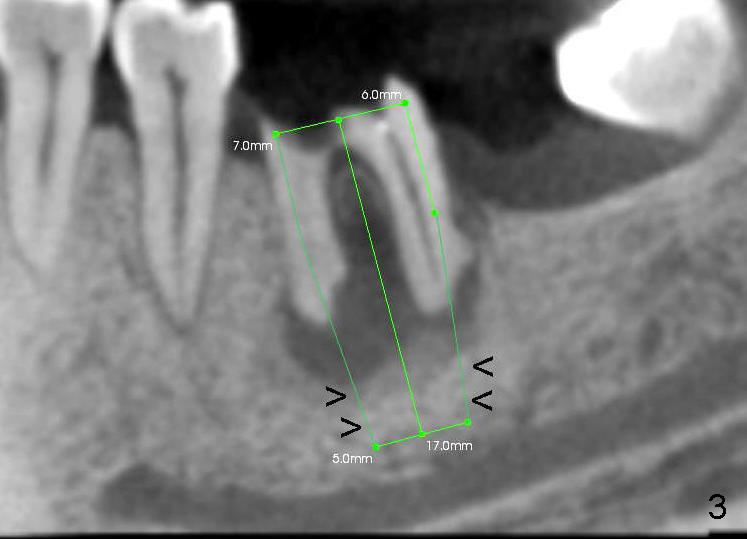

A 46-year-old female patient requests restoration of the lower left 1st molar (Fig.1). Although the patient refuses diabetes treatment, her wounds usually heal uneventfully. Her gag reflex is active. She could not tolerate a removable partial denture, which replaced the missing 2nd molar. Preop PA and CT shows extensive bone loss around the residual roots (Fig.1,2,4). It appears that extraction is simple. Immediate implant should not add too much additional trauma (Fig.3,5). Arrowheads in Fig.3,5 indicate the extent of osteotomy for implantation. With meticulous surgical manipulation, the wound should heal normally.

In addition, the patient is instructed to take Amoxicillin 500 mg tid and rinse with Chlorhexidine two days before surgery. Purulence discharges from the furca when intraligamental injection is applied. Infected granulation tissue is thoroughly curetted from the socket, followed by multiple application of Clindamycin gauze and copious irrigation. Reamers at slow speed (50 RPM) are used to save the autogenous bone, which is placed to the distal and buccal aspects of the socket after placement of 7x17 mm implant (35/40 Ncm). Large implant facilitates socket closure. Chromic suture (4-0) is used to close the wound distally, followed by application of multiple antibiotic ointment and perio dressing around the implant. The patient continues oral antibiotic and mouth rinse postop.